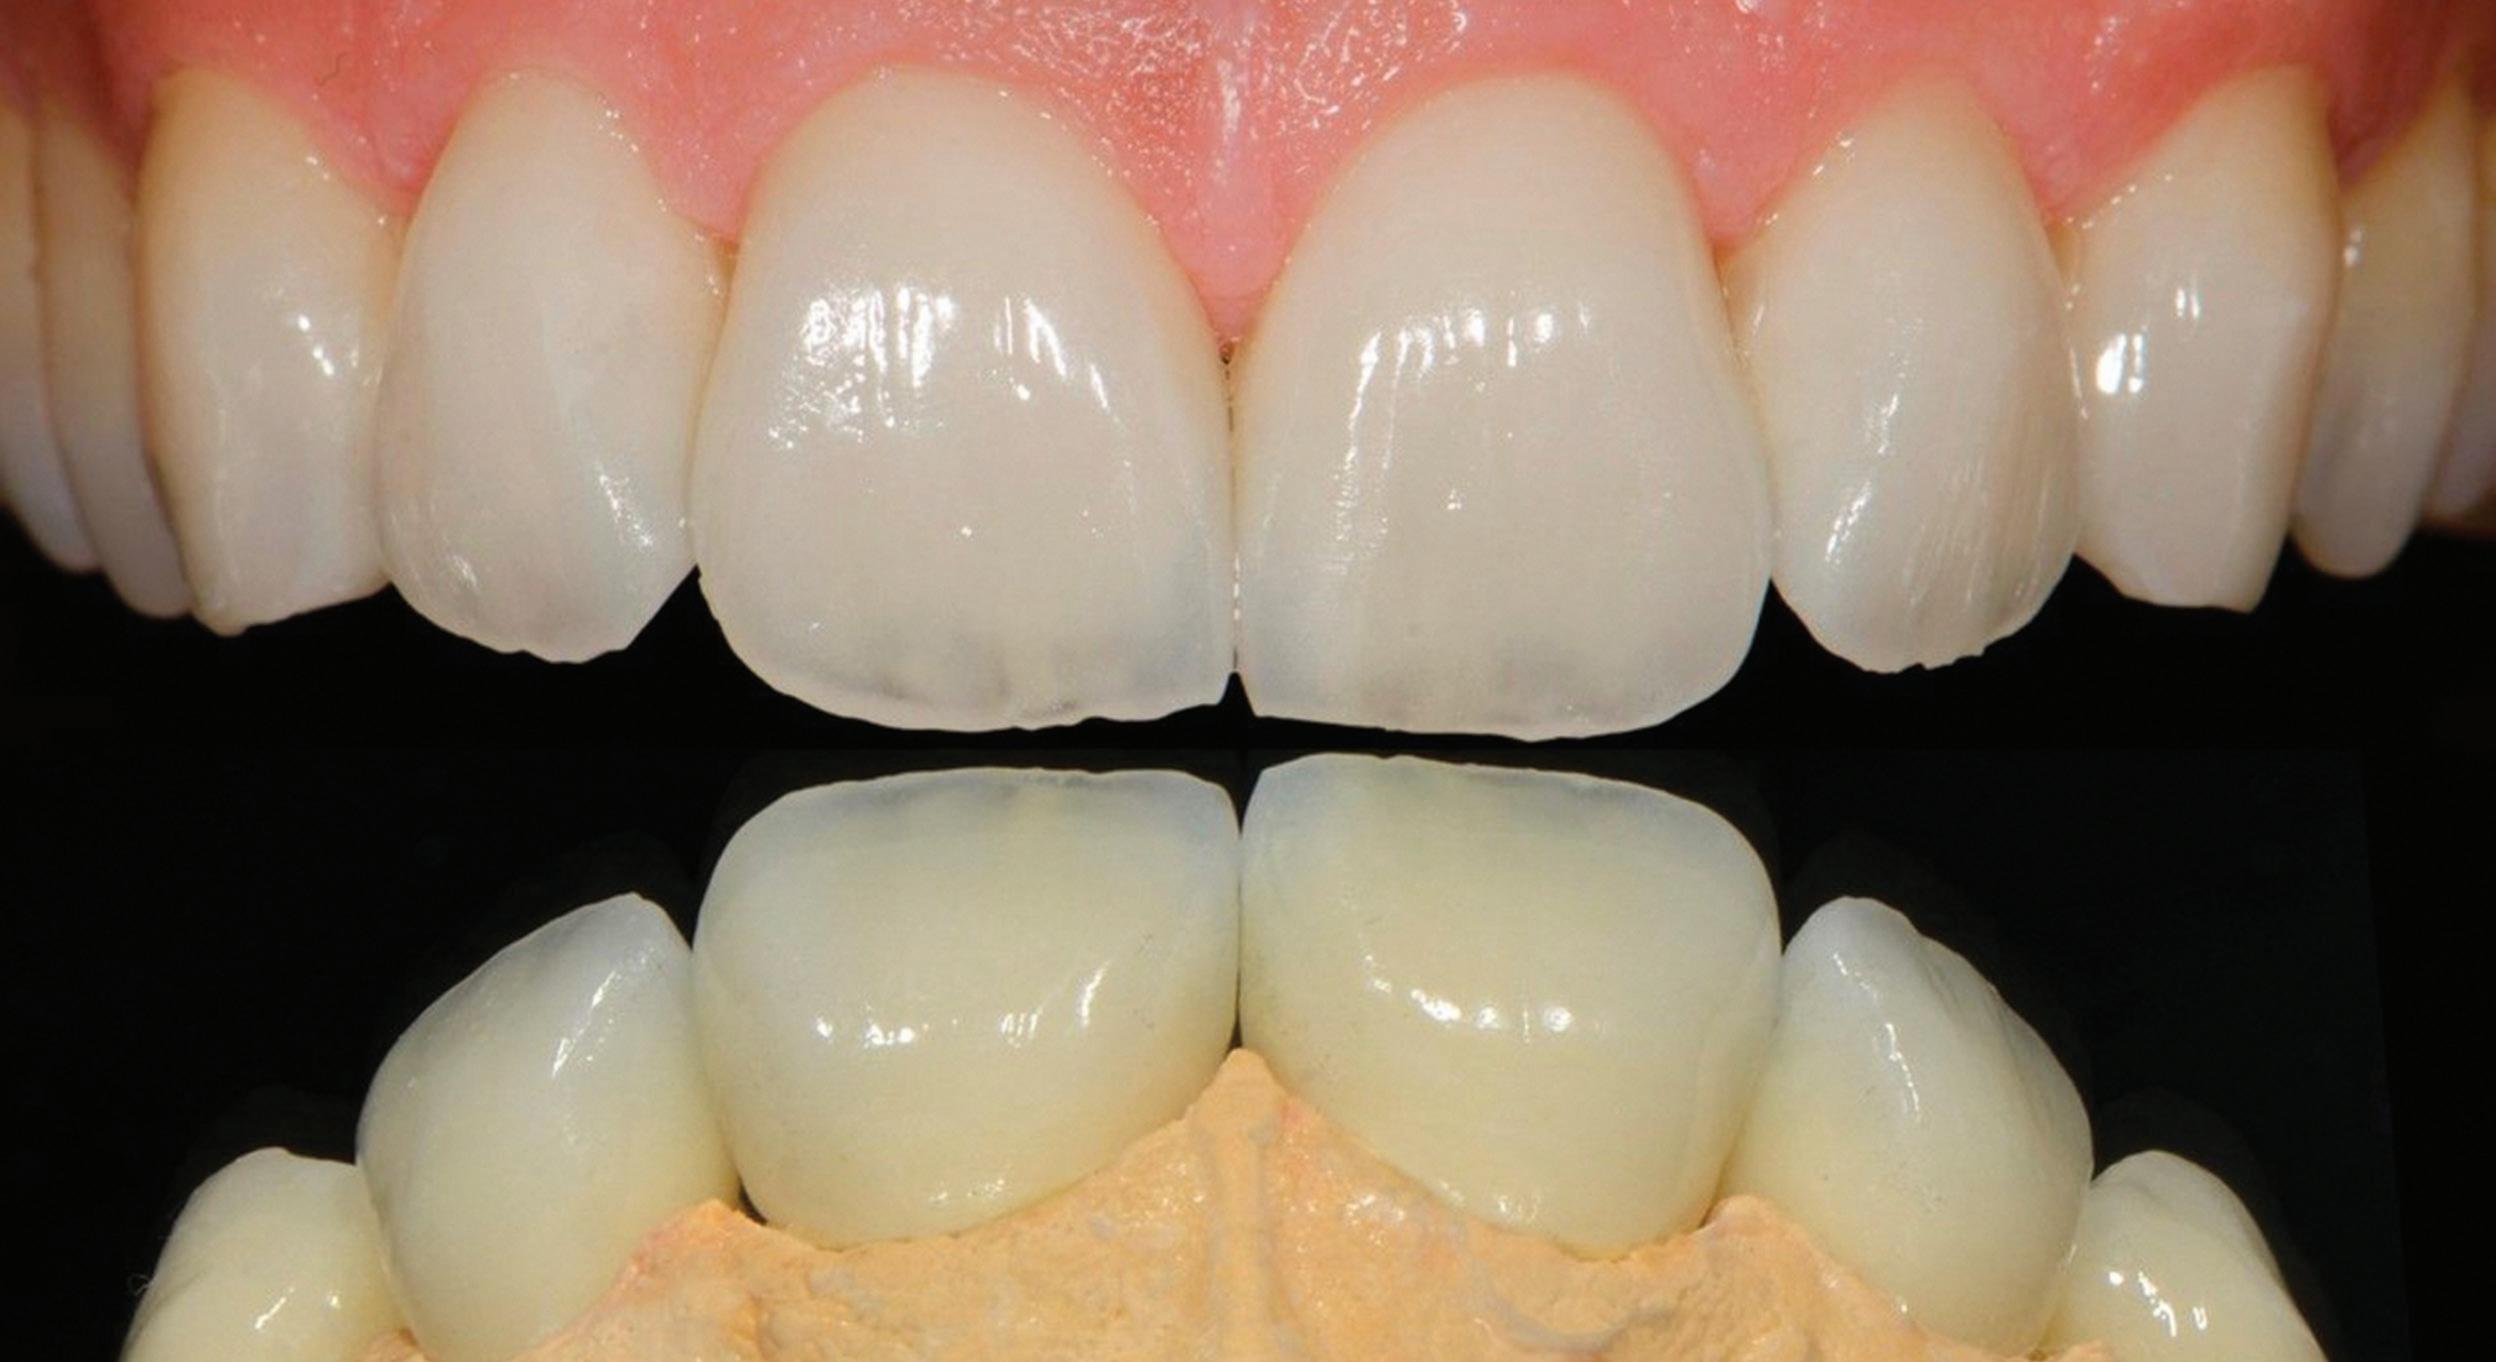

Dr Angelo Lazaris is renowned as the doyen of dental veneers... Celebrities, professionals, billionaires and every day Australians seek out Dr Lazaris when they want outstanding aesthetic excellence...

In the ALPHA TO OMEGA OF VENEERS, Dr Lazaris shares his unique, aesthetically-driven protocols and digital workflows as a unified system developed specifically to enhance clinical efficiency and predictability and eliminate any margin for error. Structured in a modular sequence, each topic is delivered as a step in a methodical, reverse-engineering process that maps out a logical pathway to achieving superior treatment outcomes with precision and confidence. Honed through comprehensive critical analysis and evolution, these protocols are universally applicable to every dentist, every patient and every case...

Angelo has developed his own complete digital protocols from inception and design through to delivery and integrated these with biomimetic adhesive dentistry and contemporary restorative materials to create a complete clinical workflow that is equally applicable to single restorations, through to complex full mouth rehabilitations, culminating in outstanding clinical outcomes in a real-world commercial environment. His innovative approach to clinical dentistry is to start at the desired